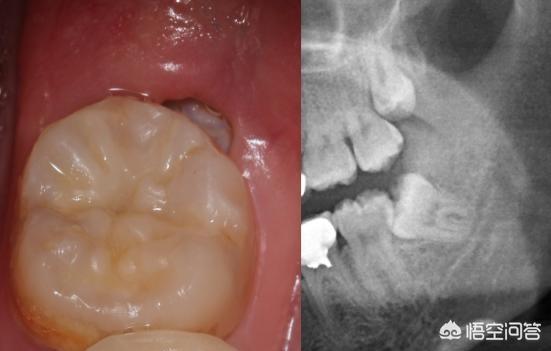

Le lendemain, la moitié de mon visage était enflée et j'ai dû aller à l'hôpital. Après l'examen à l'hôpital, le médecin a dit que mes dents de sagesse étaient enflammées et qu'il y avait des caries, également connues sous le nom de dents vermoulues.

Le médecin m'a recommandé de faire extraire mes dents de sagesse et de faire obturer mes caries. Le plombage, j'ai accepté, après tout, le milieu commence à se vider, le plombage ne peut pas. Mais j'ai refusé d'arracher la dent, ça fait un peu peur, et la dent est partie.

Un comprimé d'ibuprofène pour résoudre vos besoins urgents, au moins garder quatre heures est très confortable, mais ce n'est que temporaire, spécifique ou doivent prendre un film pour vérifier, l'un est l'inflammation des dents de sagesse, la prise de métronidazole pour récupérer, si c'est une période spéciale des femmes enceintes, il est préférable d'aller à l'hôpital pour rincer l'anti-inflammatoire, ou kin gilan bain de bouche gargle, le second est la carie des dents déclenché l'inflammation endodontique, la douleur spontanée aiguë, se dépêcher le traitement de canal.